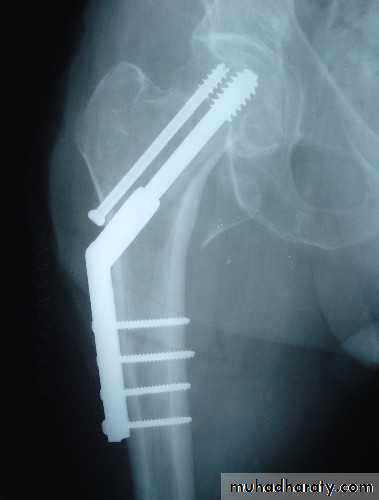

Intertrochanteric fractures (Extracapsular)

Common in elderly, osteoporotic people;most of the patients are women in the 8th decade.

In contrast to intracapsular fractures, extracapsular trochanteric fractures unite quite easily and seldom cause avascular necrosis.

Treatment

Intertrochanteric fractures are almost always treated by early internal fixation because :(a) to obtain the best possible position And

(b) to get the patient up and walking as soon as possible and thereby reduce the complications associated with prolonged recumbency.

The fracture is fixed with an angled device – preferably a sliding screw in conjunction with a plate (dynamic hip screw) or

intramedullary nail. or

95 degree screw-plate (L-Plate)

Dynamic hip screw

L-plate (fixed angle plate)